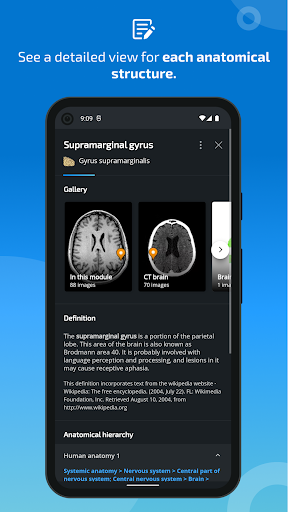

-In the details view of an anatomical structure related terms are now displayed

-New option to expand image galleries in the anatomical structure information screen.

- “Filter by”, in the details view you can now filter the images containing the anatomical structure by modality